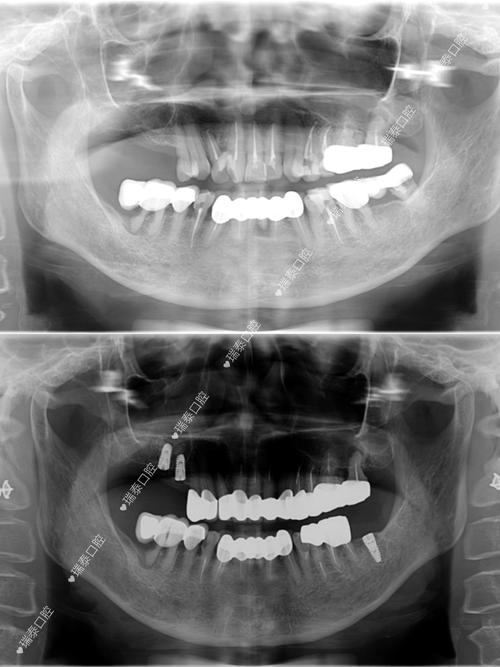

上颌5种植牙治疗周期通常为3-6个月,分四阶段完成:①术前检查与设计:通过CBCT评估牙槽骨厚度、高度及与上颌窦的距离(理想距离≥2mm,若不足需行上颌窦提升术),口内扫描获取牙列模型,结合咬合分析制定种植方案,必要时采用数字化导板辅助种植,将误差控制在0.1mm内,提高种植体植入精度。②种植手术:局部麻醉下,在缺牙区牙龈做弧形切口,剥离黏骨膜暴露牙槽骨,使用专用种植机逐级备洞(直径3.5-4.5mm,深度10-13mm,避免穿通上颌窦),将纯钛种植体(生物相容性极佳)植入牙槽骨,植入扭矩通常≥35N·cm(确保初期稳定性),生理盐水冲洗后缝合切口,术后7天拆线。③骨结合期:种植体与牙槽骨形成“骨整合”,这是种植成功的关键,上颌骨因血供相对下颌差,骨结合时间需4-6个月,期间避免种植区咀嚼受力,可佩戴临时义齿美观。④牙冠修复:骨结合完成后,行二期手术暴露种植体,安装愈合基台,2周后牙龈成型,取模制作全瓷或烤瓷牙冠(全瓷冠美观度更佳,生物相容性好),试戴调整咬合后粘固完成修复,最终实现“以假乱真”的咀嚼效果。

尽管种植牙成功率较高(95%以上),但仍存在一定风险:①感染:术前预防性使用抗生素,术后保持口腔卫生,若出现术区红肿、溢脓,需及时进行抗感染治疗和牙周基础治疗;②种植体周围炎:因菌斑堆积导致,表现为牙龈退缩、牙槽骨吸收,需通过龈下刮治、激光治疗控制,严重时需手术植骨;③上颌窦穿孔:若牙槽骨高度不足,备洞时可能穿透上颌窦,需立即停止手术,根据穿孔大小选择自体骨或骨粉植骨,延期种植;④种植体松动或失败:多与骨结合不良、咬合力过大有关,需取出种植体,3个月后评估骨条件再植。